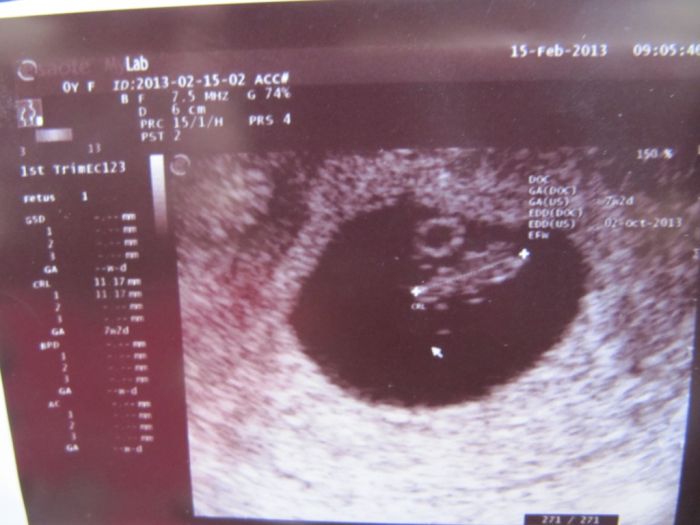

Jsme 9+5 a měříme už 2,2 cm

a už jsme viděla jak se krásně vrtí:) a taky jsme dostali těhu průkaz hurá!! Na ten screning jsem objednaná na 5.4. ale ještě nevím jestli tam půjdu ... No uvidím. Přikládám fotečku